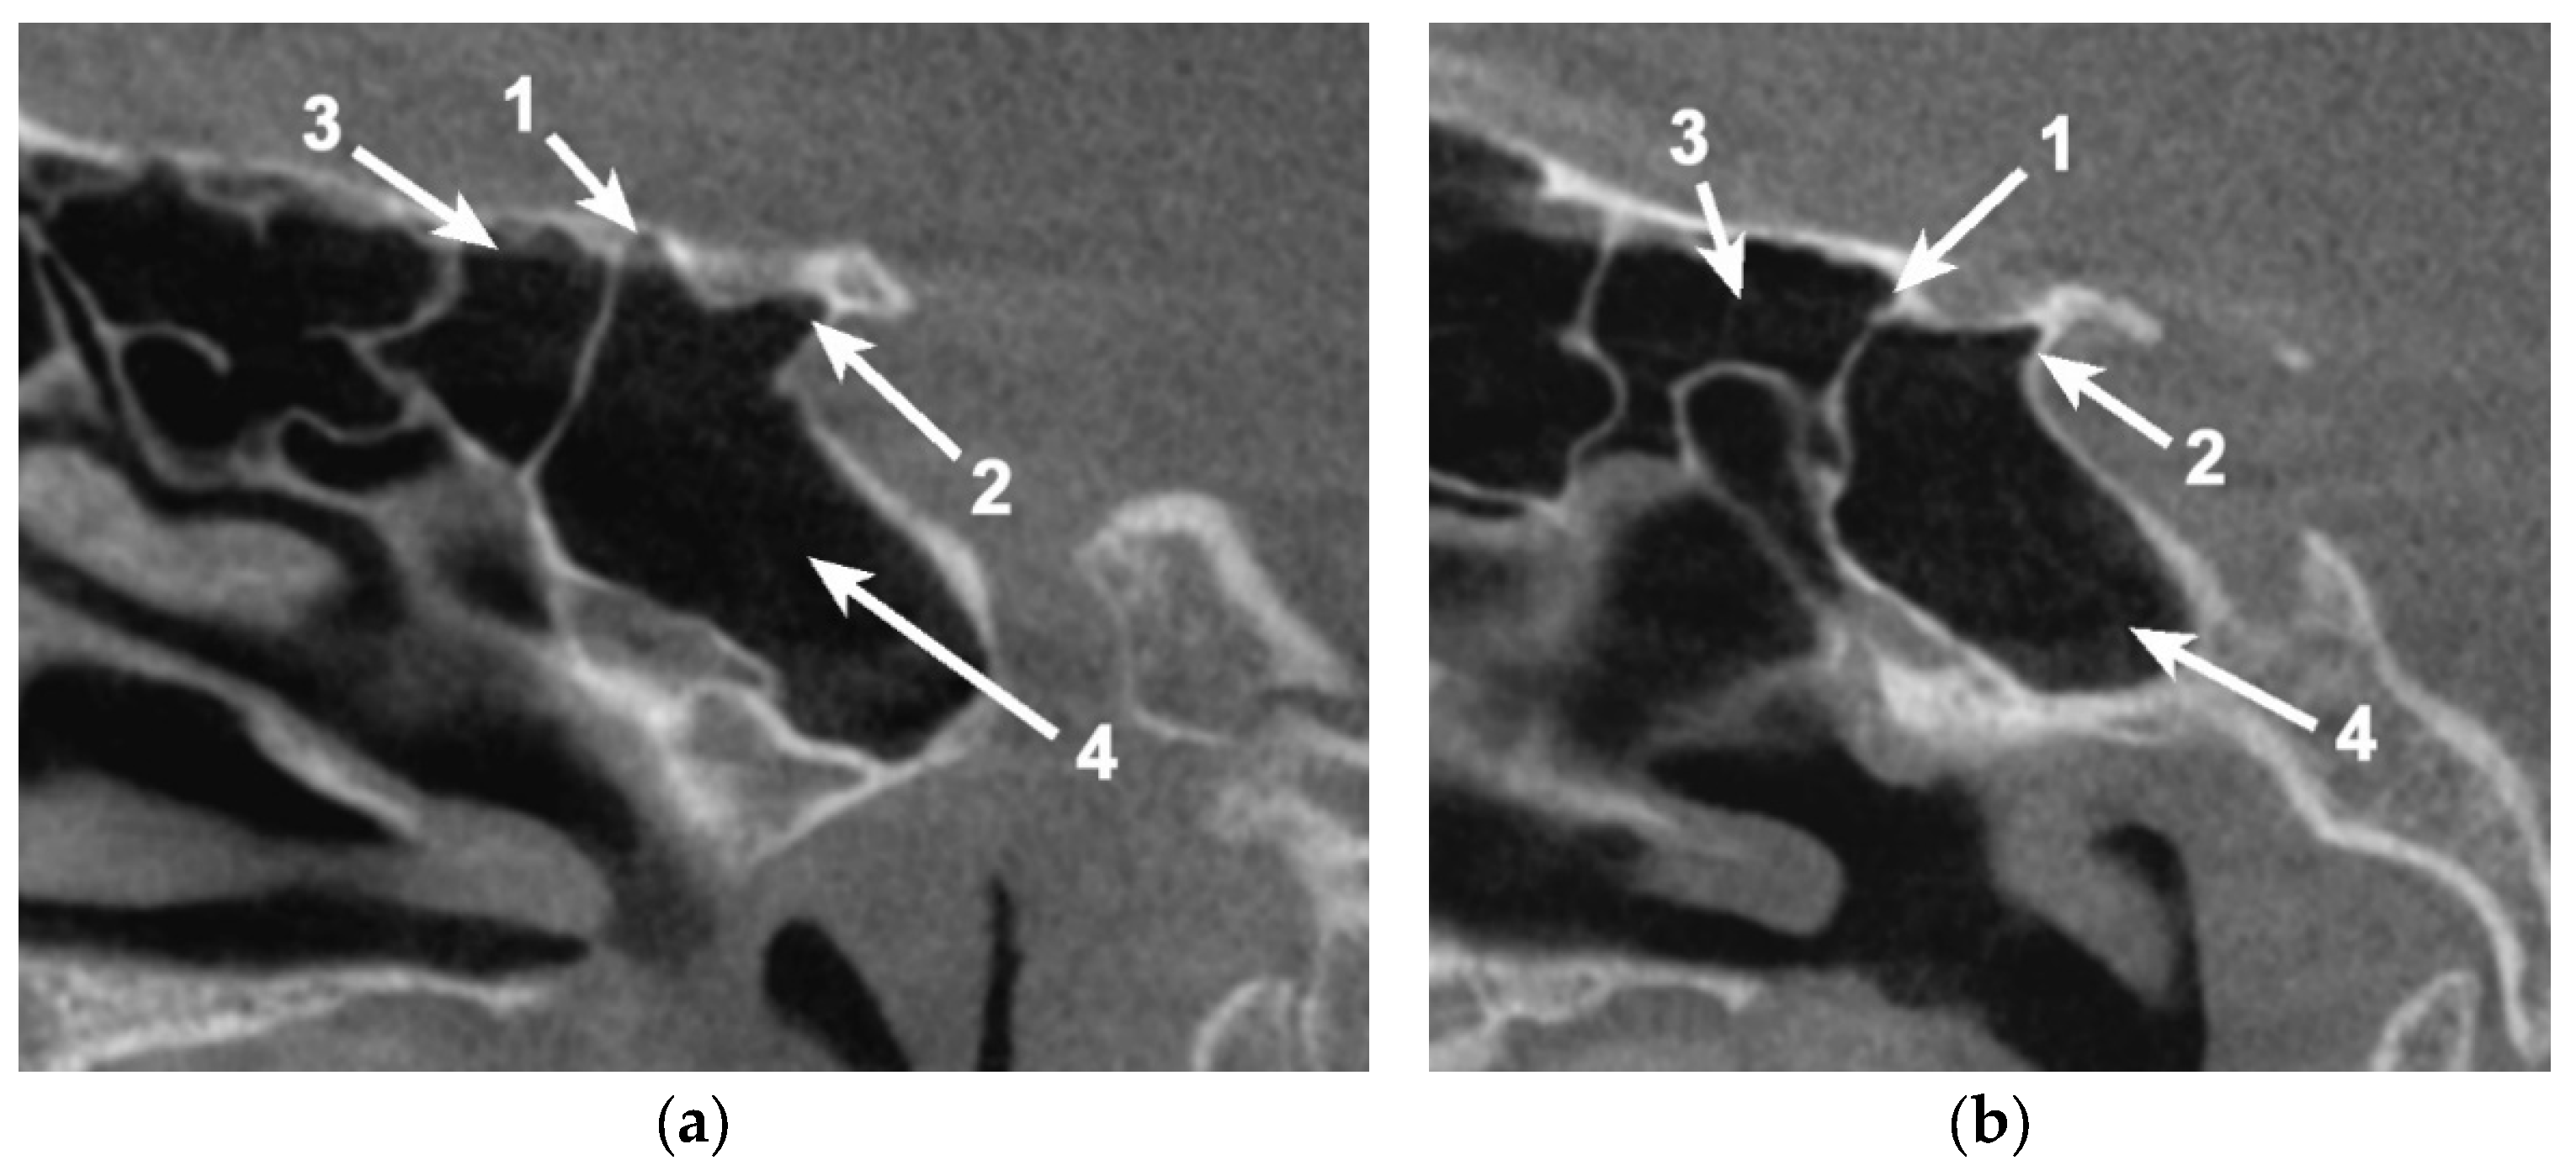

Figure 3. Bilateral sagittal CBCT reconstruction, demonstrating the pattern of pneumatization of both the optic strut (OS) and anterior root (AR). (a) Left side; (b) Right side: 1. Pneumatized AR; 2. Pneumatized OS; 3. Onodi cell; 4. Sphenoid sinus.

Figure 4. Bilateral sagittal CBCT reconstruction, demonstrating the pattern of pneumatization of both the optic strut and anterior root (AR) of the lesser sphenoidal wing. (a) Left side. (b) Right side: 1. Pneumatized AR; 2. Pneumatized OS; 3. Onodi cell; 4. Sphenoid sinus.

In 54/80 cases (67.5%), pneumatization within the OS could be identified (Figure 4). In eight cases (8.75%—six unilateral and two bilateral cases), the pneumatization of the sphenoid bone passed the OS, reaching the ACP.